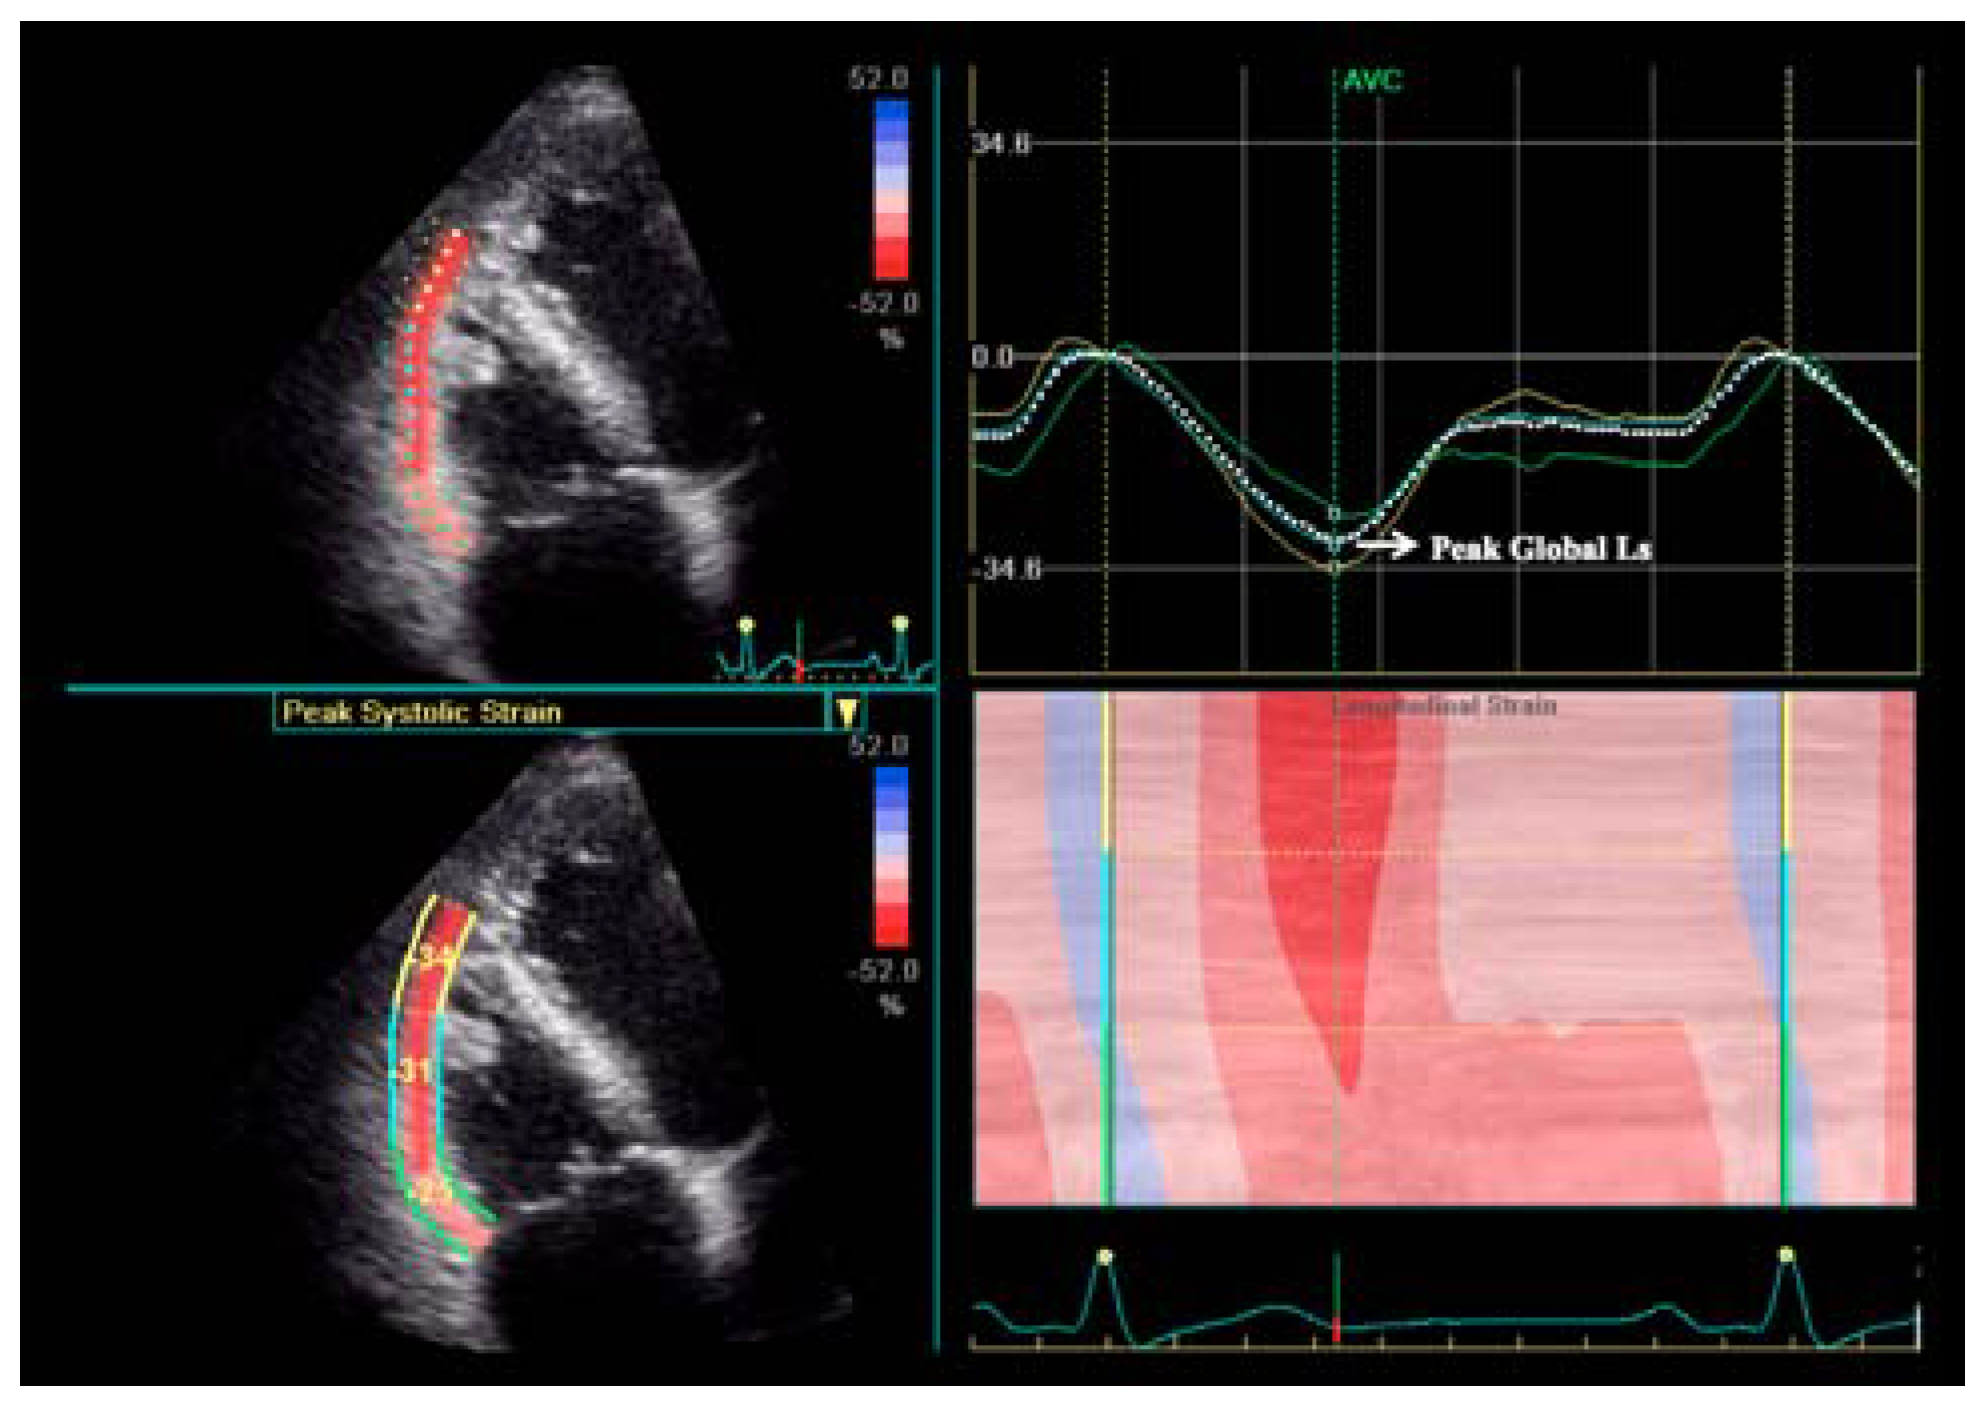

Right ventricular strain Right Ventricular Dimensions Echo Systolic and diastolic function, and rv systolic pressure. in contrast to the near conical shape of the left ventricle, the right ventricle is more. the american society of echocardiography recommendations for cardiac chamber. to assess rv dimension, volume, and function, american society of echocardiography guidelines suggest. the right ventricle (rv) has historically received less attention than. Right Ventricular Dimensions Echo.

Right ventricular strain Right Ventricular Dimensions Echo to assess rv dimension, volume, and function, american society of echocardiography guidelines suggest. Systolic and diastolic function, and rv systolic pressure. the right ventricle (rv) has historically received less attention than its counterpart on the left side of the heart,. in contrast to the near conical shape of the left ventricle, the right ventricle is more. . Right Ventricular Dimensions Echo.